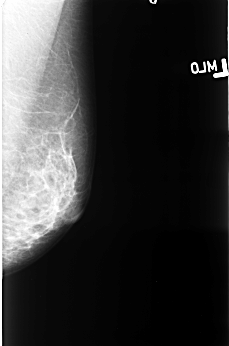

B_3403_1.RIGHT_CC

RIGHT_CC LINES 4448 PIXELS_PER_LINE 2976 BITS_PER_PIXEL 12 RESOLUTION 50 OVERLAY

FILE: B_3403_1.RIGHT_CC.OVERLAY

TOTAL_ABNORMALITIES 1

ABNORMALITY 1

LESION_TYPE MASS SHAPE IRREGULAR MARGINS OBSCURED-ILL_DEFINED

ASSESSMENT 4

SUBTLETY 2

PATHOLOGY MALIGNANT

TOTAL_OUTLINES 1

BOUNDARY